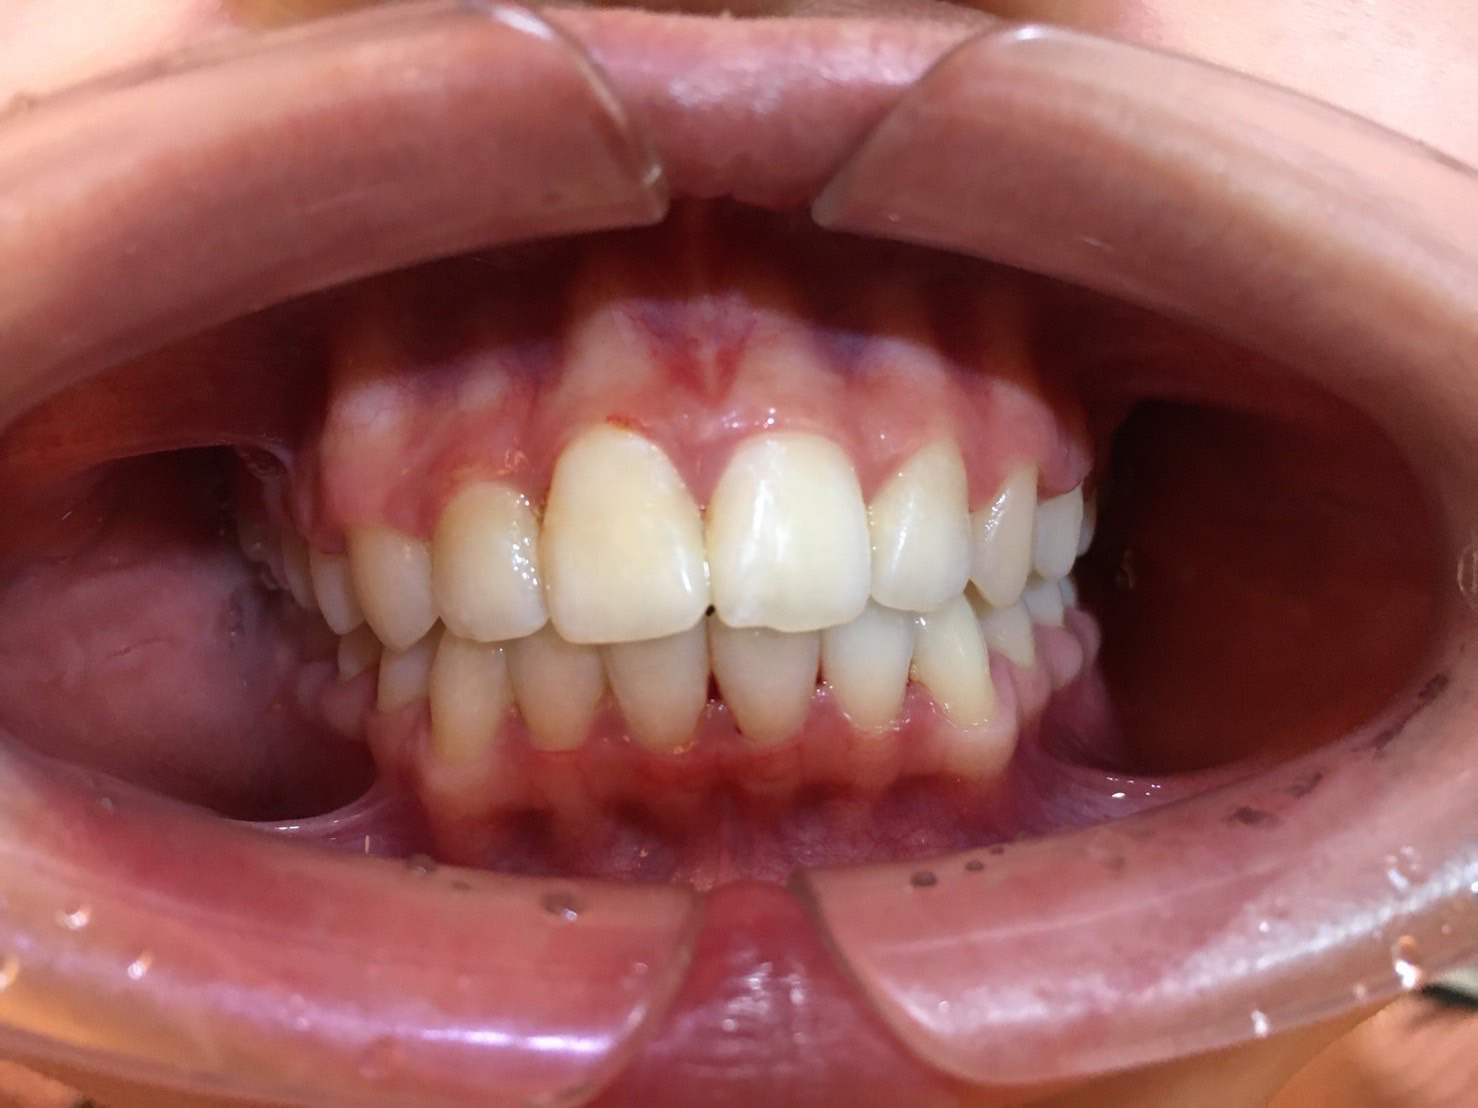

牙齒矯正